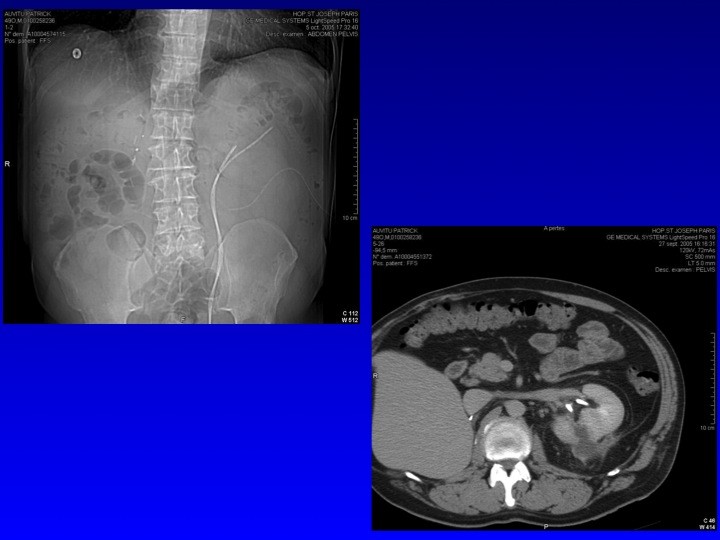

- Mini-débat : cas d’un patient jeune avec tumeur hilaire

Philippe PAPAREL (Pierre-Bénite) vs Laura POISSONNIER (Lyon)